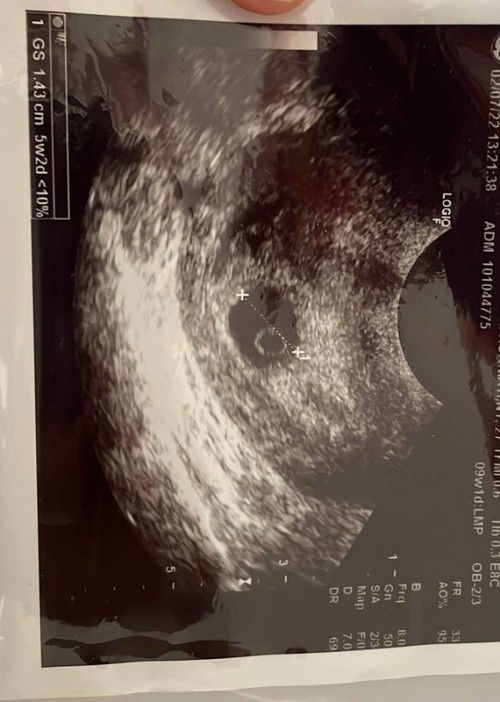

Assalamu'alaikum...sekedar sharing mungkin bunda2 disini ada yg pernah mengalami hpht sy tgl 3 mei sebelumnya sy sudah tespek dan garis dua lalu pada tgl 5 juni sy usg ternyata terdapat kantong kehamilan lalu hari ini tgl 2 Juli sy kontrol kembali ke dokter kandungan dan d usg di bagian perut masih terlihat kantung kehamilan belum ada janinnya lalu dokter melakukan usg transvaginal yg terlihat kantung kehamilan dan bakal janin dan dokter bilang tunggu 2 minggu lagi untuk usg, dan selama masa kehamilan sy saat ini tidak pernah keluar flek. Yang saya tanyakan apakah wajar jika hamil 8 minggu hasil usg transvaginal nya seperti gambar tsb. Saya takut jika BO karena ini merupakan kehamilan pertama saya :( mohon sharingnya bunda2 sekalian

bun itu hasil usg nya keterang nya baru 5w2d